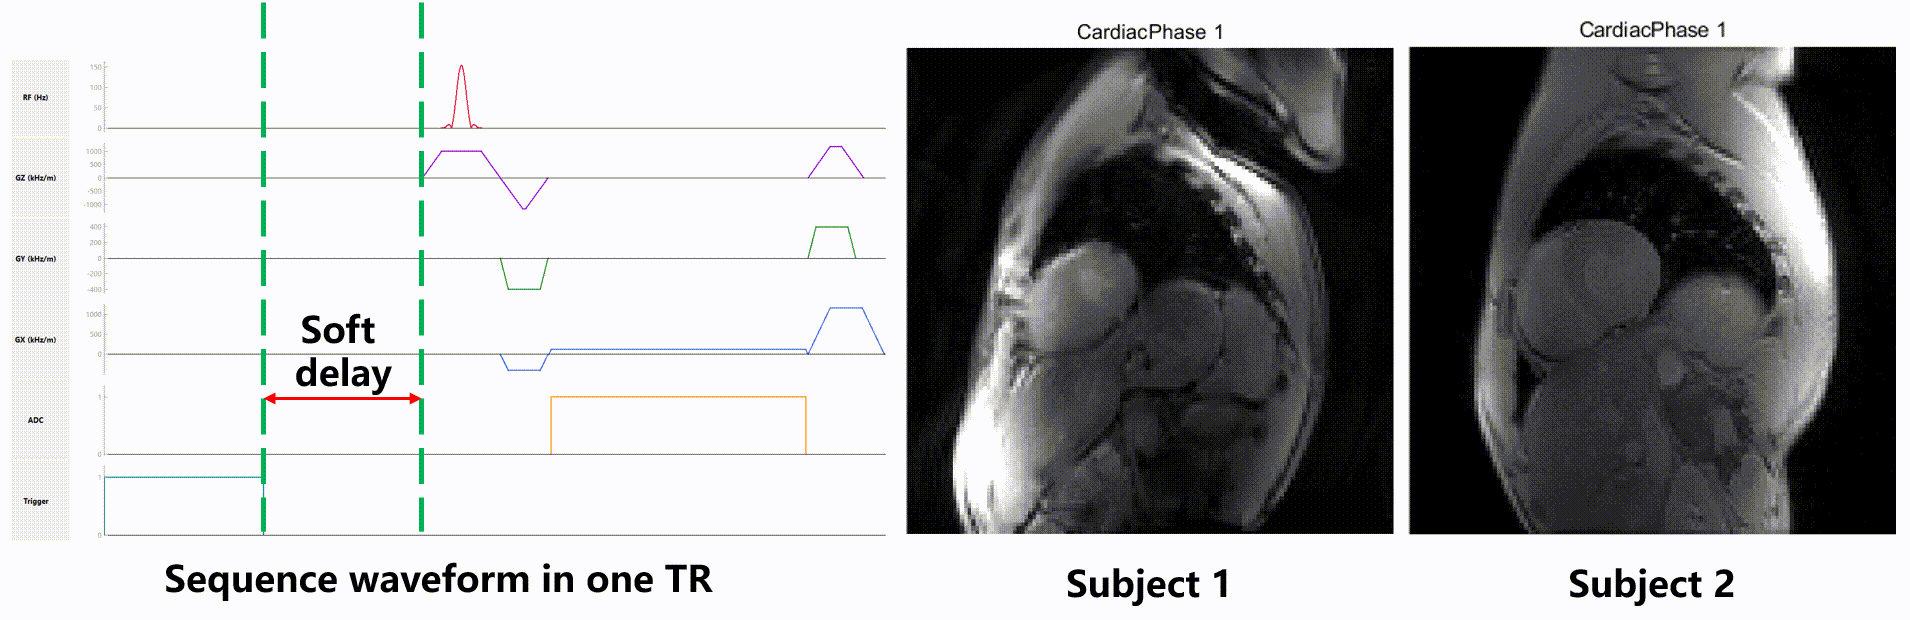

Case3: Cine

In-vivo cine pulseq sequence with soft delay, to enable scanning of subjects with different RR-intervals